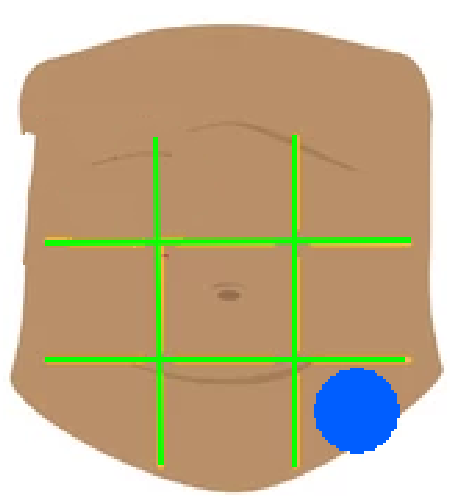

Right hypochondriac region

Left hypochondriac region

Epigastric region

Right lumbar region

Left lumbar region

Umbilical region

Right inguinal region

Left inguinal region

Hypogastric regions